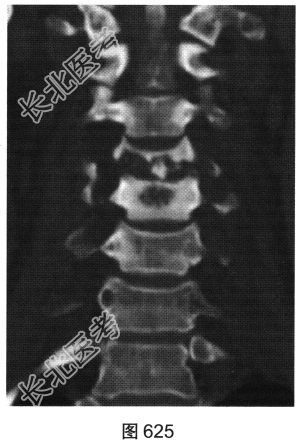

- [材料题] 患者男性,34岁,近数月乏力,偶有低热。颈部疼痛2个月余,逐渐加重,有轻压痛,颈部活动受限。

- 多项选择题2.[提示]患者行颈椎X线、CT和MRI检查,见图623~图628。首先应考虑患者为下列哪种疾病( )